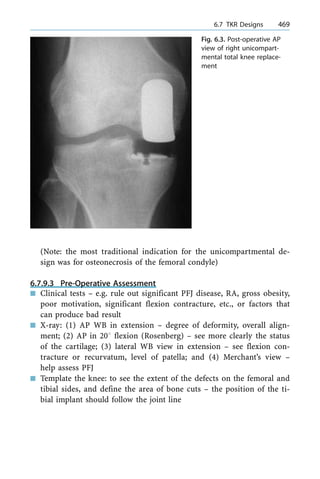

greatest potential to normal wrist mechanics (PRC is a reasonable

way to go if reduction cannot be achieved, provided head of capitate

is not significantly injured ± which alas may require fusion if the

head of the capitate is abnormal)

3.4.12.1.12 Principle of Treating Chronic Injury

n Reducible: ligamentous repair

n Fixed ± intercarpal fusion (also in athletes/manual workers)

3.4.12.1.13 Options in Late Static Chronic Instability

n Capsulodesis (may stretch out with time)

n Local fusion ± adjacent OA

n Total fusion

n Proximal row carpectomy (salvage in SLAC wrist with old non-union)